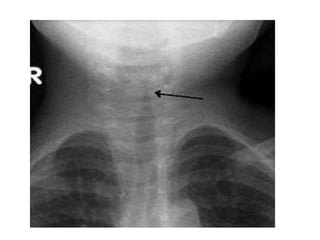

Diagnóstico:

• Es 100% clínico con exploración física

• No están recomendados estudios de

laboratorio ni radiológicos de rutina (en

dudas si)

• 16.

Diagnóstico: • Es 100%clínico con exploración física • No están recomendados estudios de laboratorio ni radiológicos de rutina (en dudas si) • El estridor no es único de LTA y refleja obstrucción en zonas superiores.